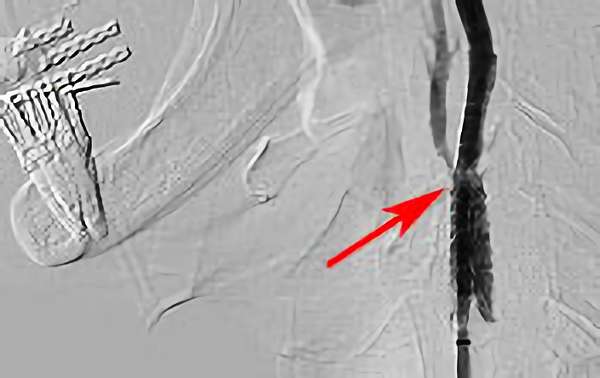

'18年3月27日

左内頚動脈狭窄症

60代

大阪府の病院

手術写真

治療

前

中

後